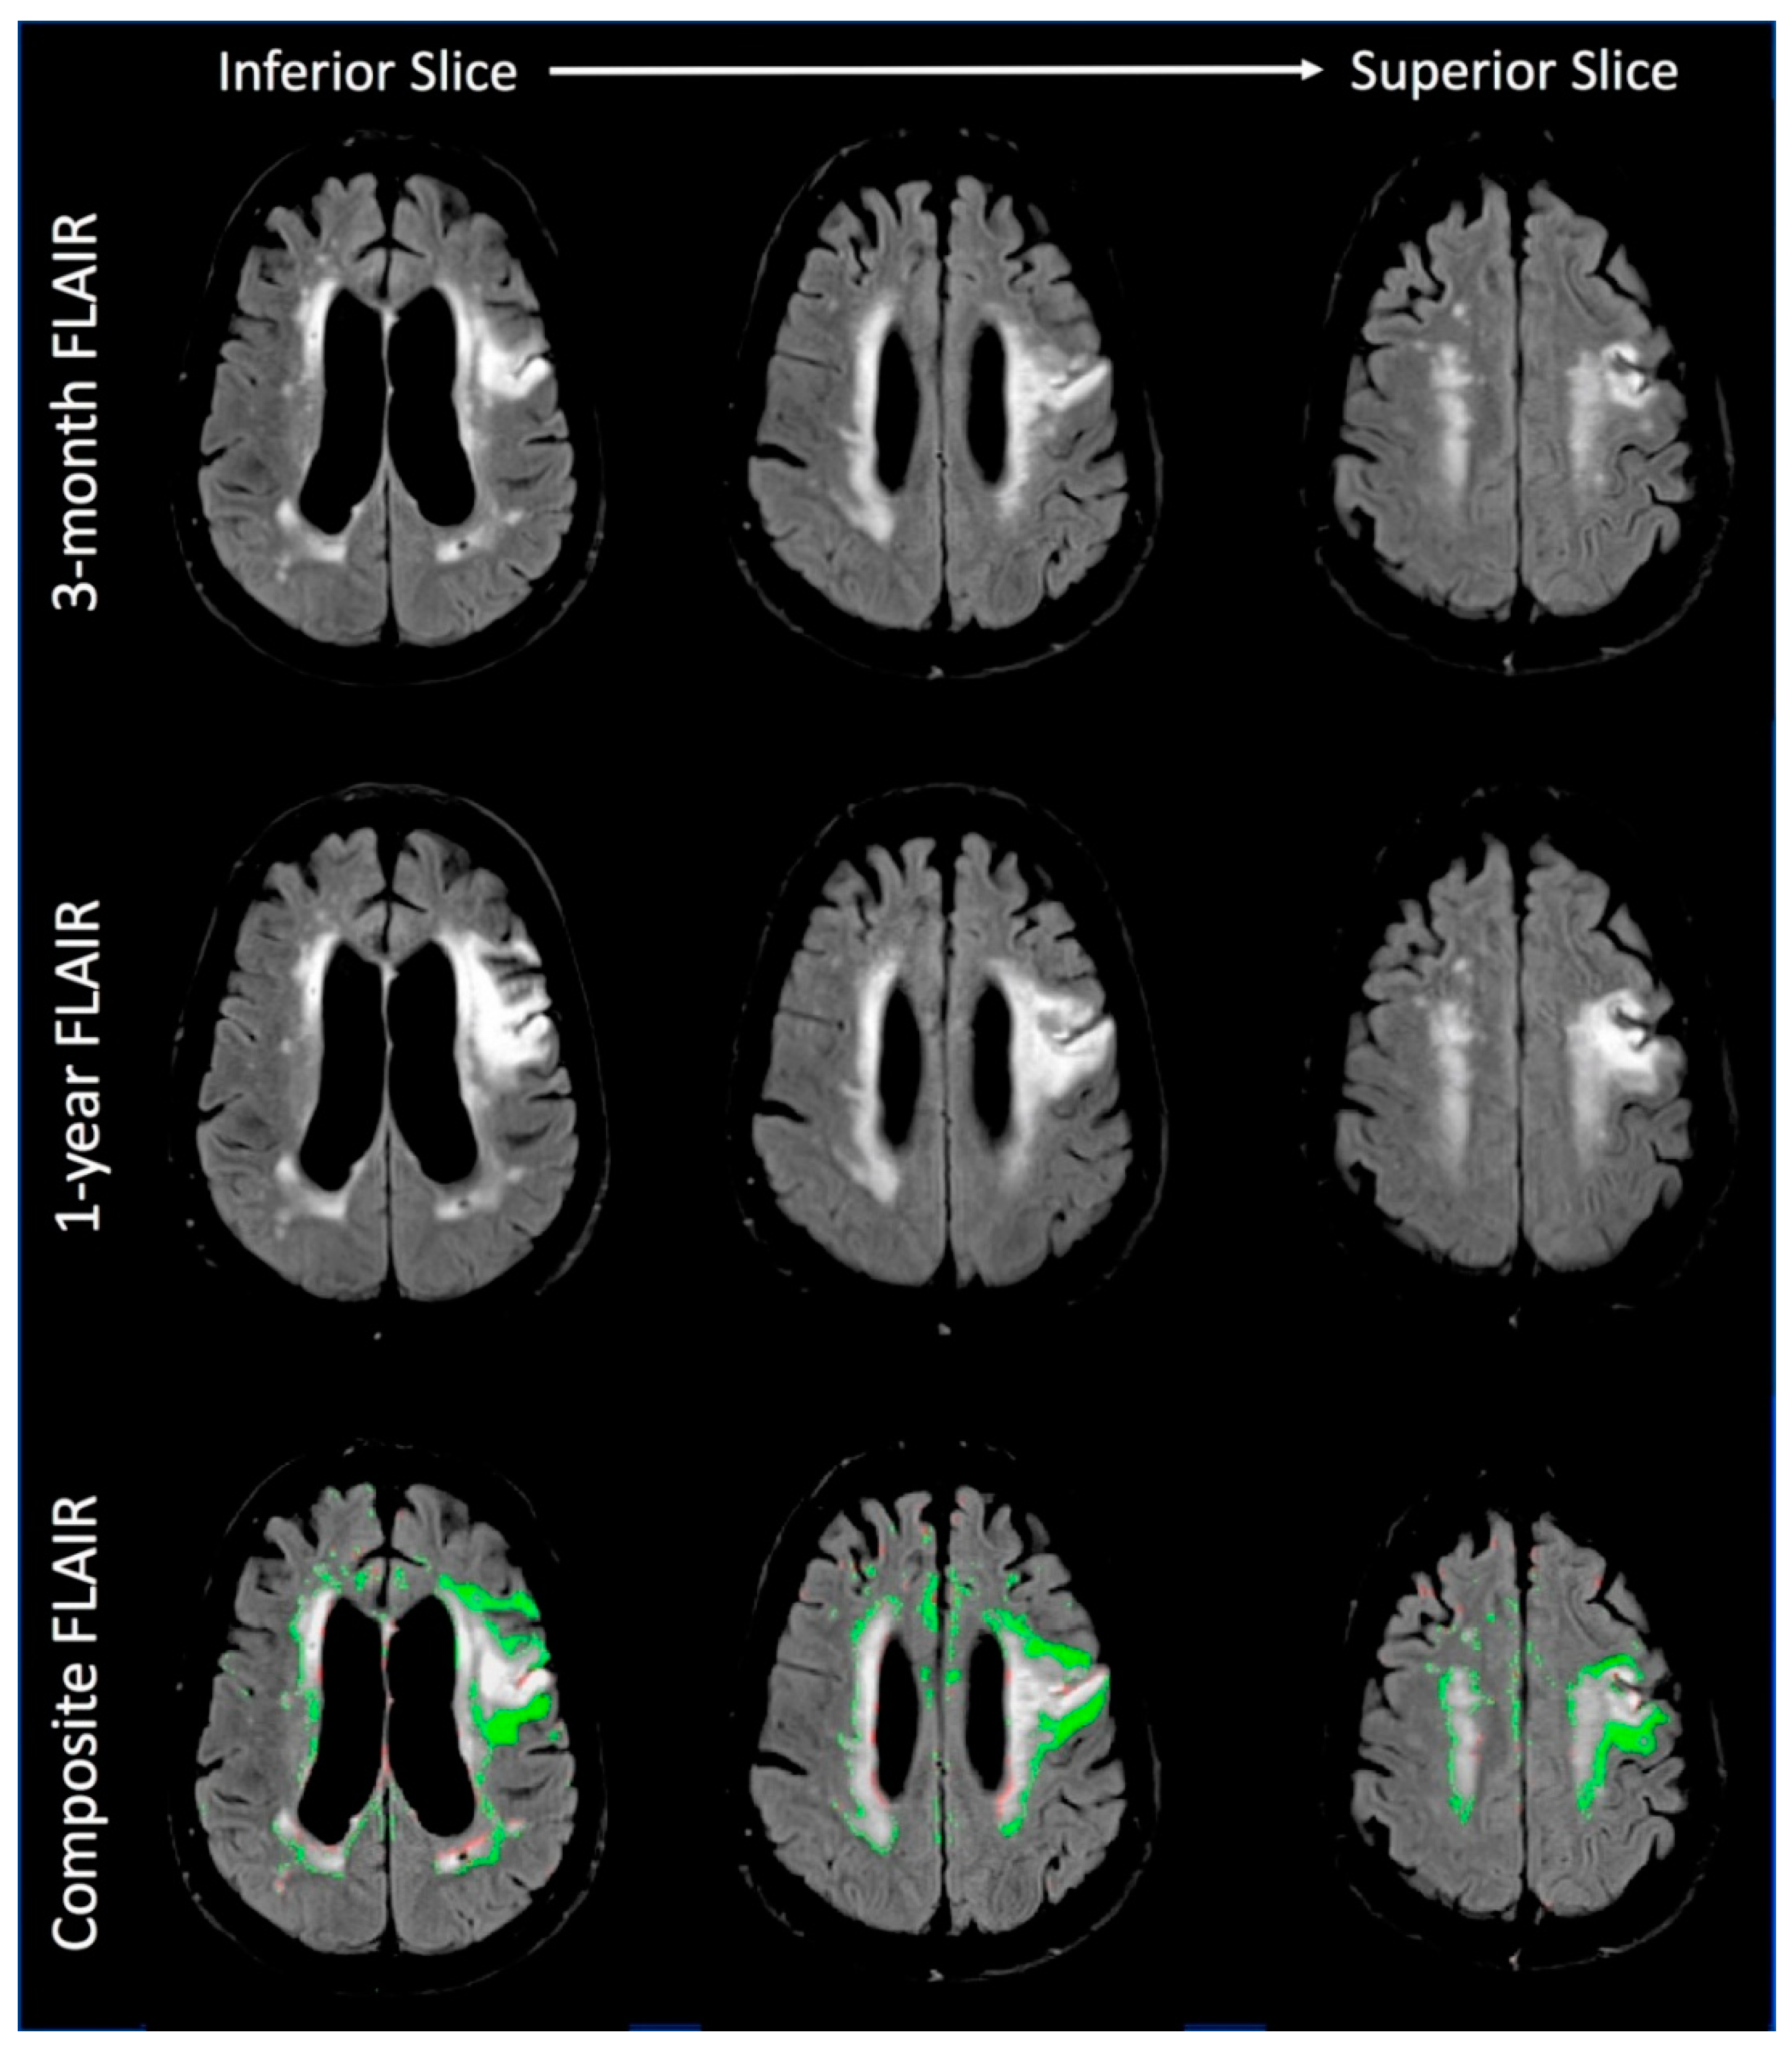

3.1.1. Imaging Findings